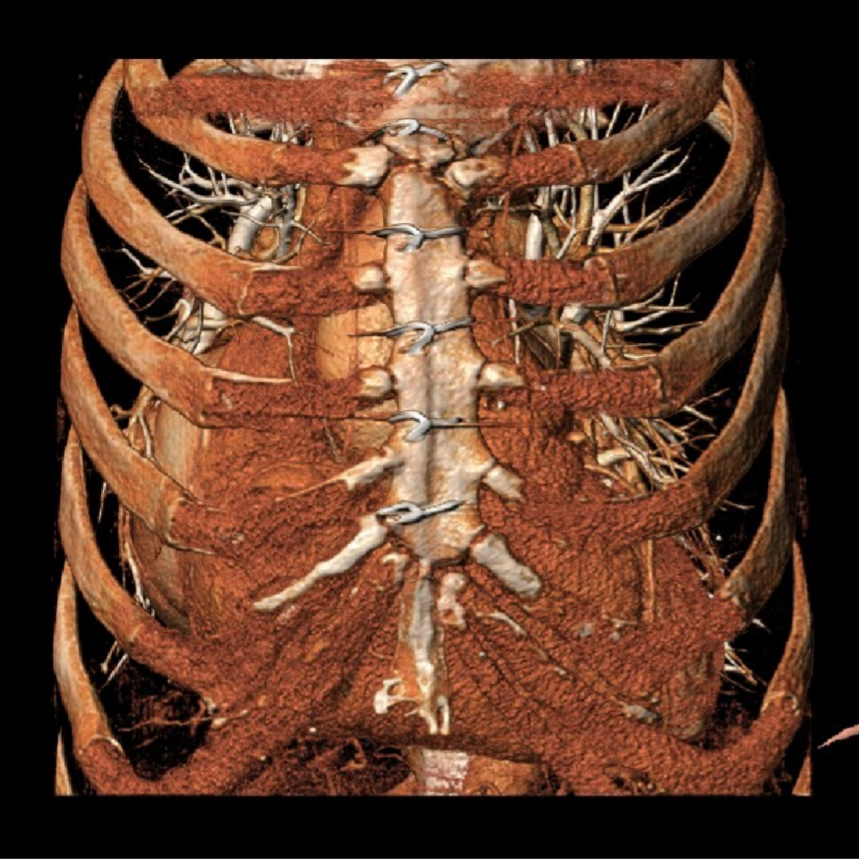

辅助检查:主动脉CTA可见腹主动脉夹层。

该病例同时合并腹主动脉夹层,团队同期成功实施“腹主动脉夹层腔内隔绝术”,通过微创方式置入覆膜支架,有效隔绝夹层破口、重建主动脉真腔,避免了传统开放手术的巨大创伤。对于此类主动脉瓣与二尖瓣双瓣衰败合并主动脉夹层的高危患者,二次开胸手术风险极高,而徐平、林明山教授团队凭借ScienCrown瓣膜系统的全可回收与短瓣架特性,结合经心尖途径,实现了心内双瓣膜置换与主动脉疾病介入治疗的一站式整合。为复杂心血管疾病患者提供了更具安全性、有效性和微创性的治疗新策略。